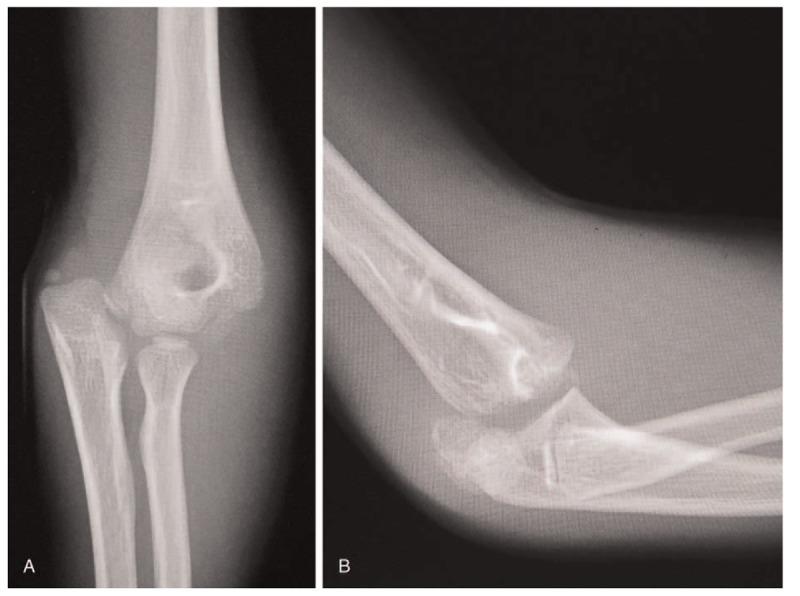

Posteromedial dislocations of the elbow with lateral humeral condylar fractures (LCFs) are uncommon, and only isolated cases have been reported in the English-language literature. Because of the complex radiolucent cartilaginous structures and late-appearing ossification centers, radiological diagnosis of elbow dislocations with LCF in children is challenging.

We report three children with posteromedial elbow dislocation: two patients with Milch type I and one patient with Milch type II LCF.

In our report, radiographs showed only a small bone fragment, and arthrography or computed tomography were helpful diagnostic aids in cases 1 and 3. In contrast, the patient in case 2 was initially misdiagnosed as having an epiphyseal separation of the distal humerus, and open reduction and internal fixation through the posterior approach revealed Milch type II LCF.

In case 1 and 3, Milch type I LCFs, open reduction and internal fixation was performed through the posterolateral approach. On the other hand, in case 2, Milch type II LCF, open reduction and internal fixation was performed through the posterior approach.

Poor reduction of Milch type I LCFs resulted in incongruity of the articular surface and poor cosmetic results in two patients. In case 2, Milch type II LCF, plain radiographs showed adequate healing without elbow deformity and the clinical result was excellent.

Because LCFs are intra-articular fractures, anatomical reduction is crucial for satisfactory outcomes. We promote awareness of this injury, especially posteromedial dislocation with Milch type I LCF. Preoperative evaluation is helpful for achieving satisfactory outcomes, and open reduction and internal fixation through an anterolateral approach might be most appropriate for Milch type I LCFs.